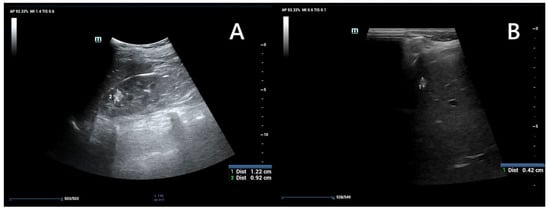

5.1. Renal Ultrasonography

Ultrasound is widely recommended as a first diagnostic approach, helpful in detecting and monitoring lesions within kidney and other accessible parenchymal organs (Figure 4), and differentiating between their solid or cystic structure. When performed by an experienced operator, it is often sufficient for evaluating simple cysts; however in patients with large body mass, thick cystic septa, or not entirely anechoic lesion contents, further assessment with CT or MRI is recommended [44,47]. The kidney should be carefully scanned in both coronal and axial planes to ensure visualization of areas potentially obscured by artifacts, such as colonic gas or rib shadows [47].

Figure 4. An ultrasound of a 13-year-old boy. Kidney with focal lesions with features suggestive of AMLs (A). Multiple oval hyperechoic lesions within the liver—most likely AMLs (B).

AMLs in ultrasound typically appear as hyperechoic to renal parenchyma, homogeneous lesions, but their appearance can vary depending on the relative composition of fat, muscle, and vascular tissue [48]. The imaging appearance is non-specific, as up to 8% of renal cell carcinomas (RCCs) can also be hyperechoic, and confirmation by CT or MRI is recommended. However, it can provide valuable indicators: if the tumor is less than 3 cm and an acoustic shadow is present, angiomyolipoma is the most likely diagnosis. In contrast, the presence of a hypoechoic halo and intratumoral cysts suggests clear cell renal carcinoma (CCRC) [44,47,48]. Atypical or fat-poor AMLs require diagnostic evaluation with other, more advanced imaging modalities, as ultrasound images are varied and non-specific [48].